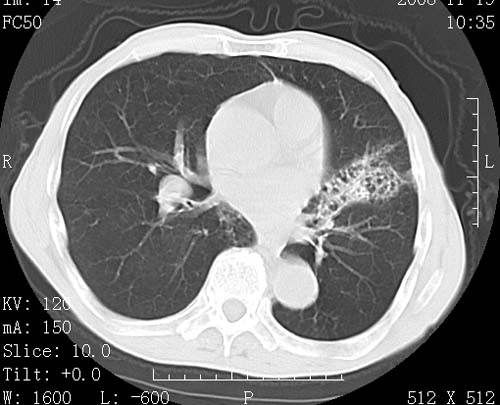

标题: CT16691:m 67 胃镜确诊食管下段及贲门癌 [打印本页]

标题: CT16691:m 67 胃镜确诊食管下段及贲门癌

术前查体,双肺部结节是转移?结核?请点评

转移 隆突下淋巴结亦肿大

首先考虑转移,纵隔内淋巴结亦肿大;

1)符合食管癌表现。2)两肺及纵隔淋巴结多发性转移瘤。3)左肺上叶舌段及两肺下叶炎症感染。

食管癌伴双肺转移,评述:肺部毛细血管网丰富,全身血液均快速流经肺部,癌细胞容易过滤定植,形成转移瘤,影象特点为以毛细血管末梢为中心的结节灶,边缘光滑锐利,少见有中心空洞着,不同来源的转移瘤可有各自特点,如甲状腺癌为双肺弥漫性微结节,本例有原发灶,双肺影象灶典型,左肺舌段条带状网格样伴胸膜天幕征,可视为癌性淋巴管炎。